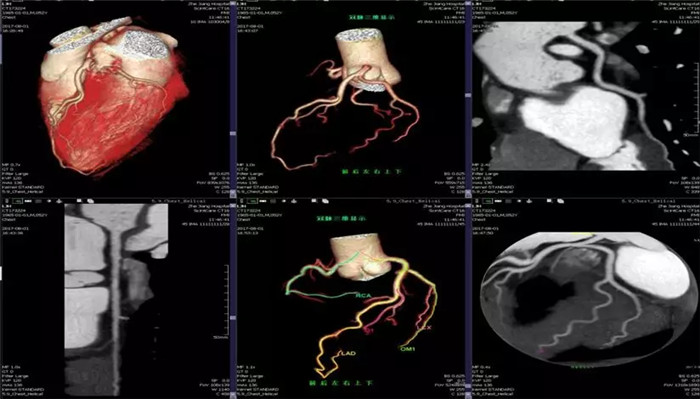

·心臟掃描應(yīng)用

·全面臨床功能